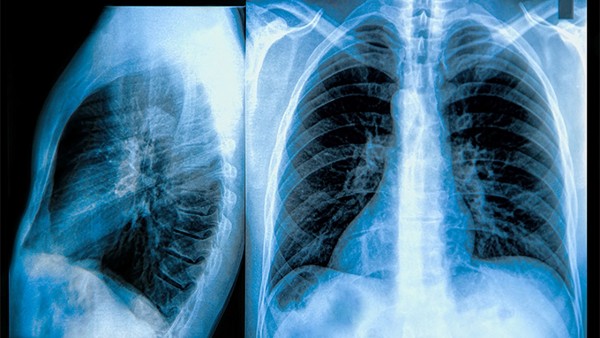

慢性阻塞性肺病是一种具有气流阻塞特征的慢性支气管炎和(或)肺气肿,可进一步发展为肺心病和呼吸衰竭的常见慢性病。25味肺病丸可用于治疗肺部疾病。25味肺病丸能修复肺功能吗?25味肺病丸能治疗慢性阻塞性肺疾病吗?

二十五味肺病丸是由檀香、挂钩木、石灰华、山奈、红花、葡萄、章牙菜、甘草、兔耳草、沙棘膏等25种中成药制成的。二十五味肺病丸具有清热消炎止咳的功效。临床上可用于治疗各种肺病引起的咳嗽。咳嗽患者伴有胸部疼痛,部分患者伴有发热、呼吸急促、咳痰脓血。对盗汗患者使用二十五味肺病丸也有较好的效果,尤其是肺结核引起的盗汗。出现心悸、心悸、四肢麻木、嘴唇麻木、恶心等症状的,应减少或停止服用25味肺病丸。